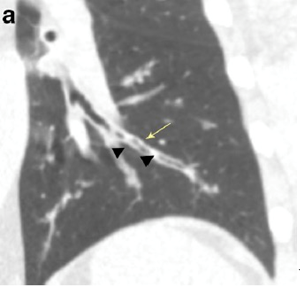

支气管炎引起的支气管壁增厚形成的双轨征(黄箭头),支气管内的粘液栓(黑箭头)[6]